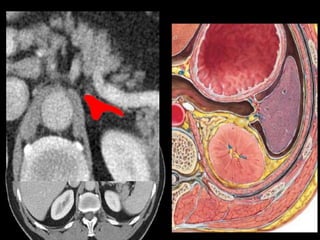

SoftTissue Structures: Subtle on

KUB.

Right common iliac

vein.

CT cross sectional

anatomy.